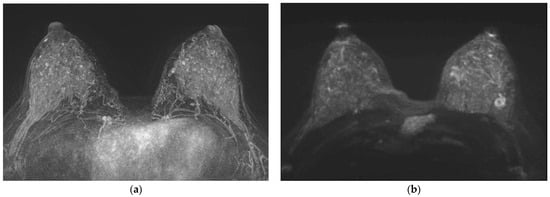

2.3. Image Analysis